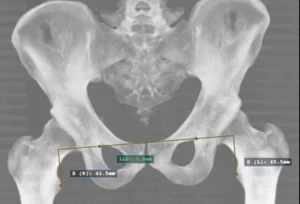

Most of us assume that our legs are the same length — after all, why wouldn’t they be? But in

Leg length differences (LLD) are surprisingly common in children — and even small discrepancies can subtly change the way young